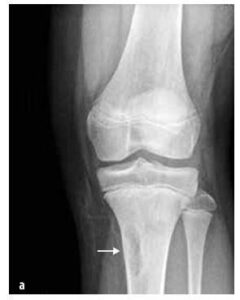

Obrázok č. 7

Neosifikujúci kostný fibróm

Benígne nádory

Tieto sa vyskytujú u detí častejšie ako malígne nádory, napr. nádory kostí (osteoidný osteóm, osteoblastóm, eozinofilný granulóm), nádory spojivového tkaniva (fibrózna dysplázia, neosifikujúci fibróm (pozri obrázok 7)), kostné cysty, nádory chrupavky (osteochondróma, enchondróma, chondroblastóm) a iné (synoviálny hemangióm a pigmentovaná villonodulárna synovitída).